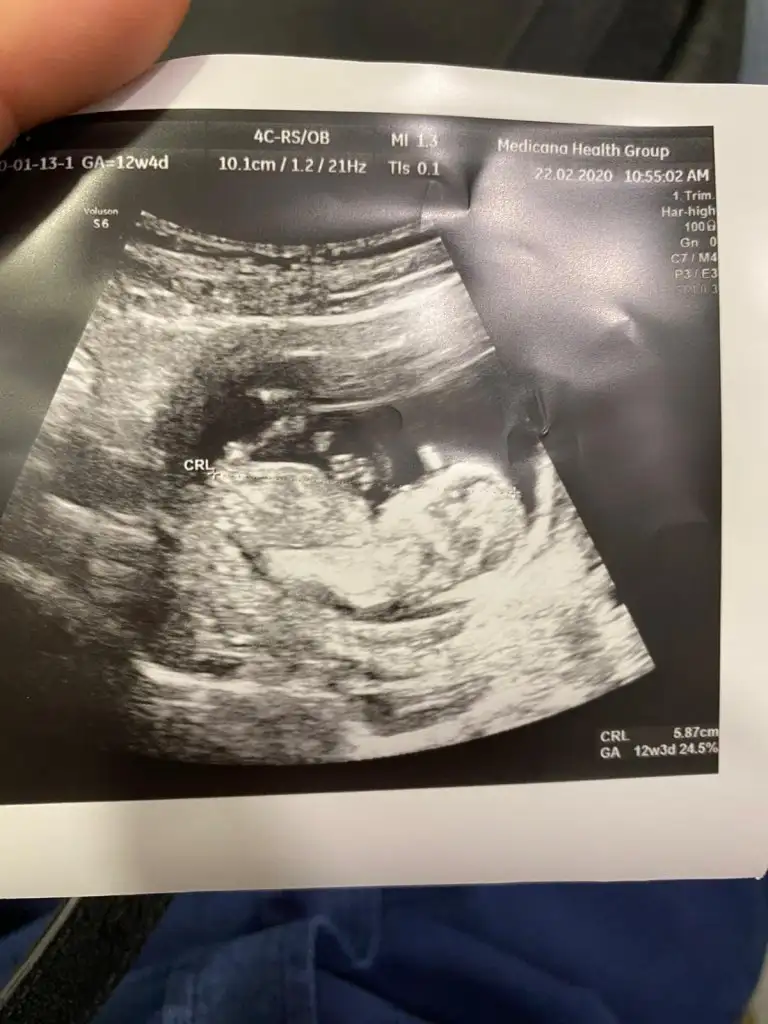

Dr + tam nuba denk getirmiş başka usg varmı12+4 banada yorumlarmisijizIkra meyra

Baska yokDr + tam nuba denk getirmiş başka usg varmı![]()

Bu göre kız ama tutmayabilir tekrar usg olursa paylaşın .usteki 12+3 usg de kafa yapısı kız gibi ama nub göremiyorum .13+ usg olursa paylaşırsınızBaska yok![]()

Bu göre kız ama tutmayabilir tekrar usg olursa paylaşın .usteki 12+3 usg de kafa yapısı kız gibi ama nub göremiyorum .13+ usg olursa paylaşırsınız![]()